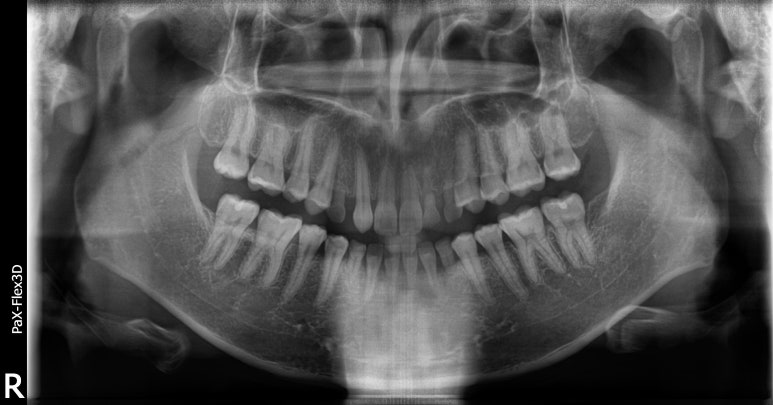

디데이치과 네비게이션임플란트 시술 전, 시술 중 엑스레이 사진

위 환자분은 앞니에 임플란트를 식립하신 환자분이라 조금 더 세밀한 식립이 가능한 네비게이션 임플란트로 수술을 진행하셨습니다.

이처럼 보다 섬세하고 세밀한 식립이 필요한 치아에 임플란트 수술을 진행할 경우에도 네비게이션으로 수술을 고려해볼 수 있습니다.